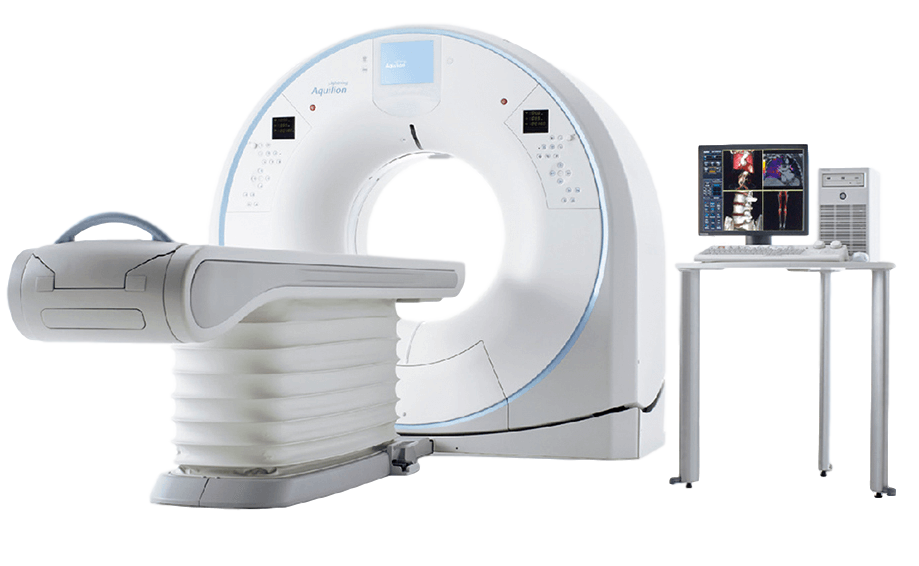

Компьютерный томограф Aquilion Lightning 80 Canon представляет собой систему, обеспечивающую съемку на 80-ти срезах с толщиной 0,5 мм и периодом полного оборота 0,6/0,5 сек., что обеспечивает исключительное качество получаемых изображений при значительном пространственном разрешении. Незначительная степень облучения обеспечивается применением специальной технологии.

Компьютерный томограф Aquilion Lightning 80 Canon укомплектован детектором с полем охвата 20 мм, что предоставляет исследователю новые клинические возможности. Мощный генератор рентгеновских лучей, апертура гентри 780 мм и минимальная высота стола 32 см с функцией механизированного перемещения влево-вправо на 42 см предоставляют возможность проводить обследование даже очень полных пациентов. Современная рентгеновская трубка обладает существенной интенсивностью охлаждения, что позволяет осуществлять непрерывно даже самые сложные и длительные манипуляции.

Гентри Aquilion Lightning предлагает инновационные разработки, улучшающие сканирование пациентов, обеспечивая при этом превосходную работоспособность и безопасность работы для техников.

Верхушка кушетки может быть опущена до минимальной высоты 312 мм для облегчения загрузки и переноски пациента с инвалидной коляски или кровати.

Небольшой размер Aquilion Lightning позволяет устанавливать его в труднодоступных помещениях, максимально расширяя существующие макеты и рабочее пространство.

Благодаря конструкции Gantry, сконцентрированной на меньшем пространстве для установки и низком потреблении энергии, Aquilion Lightning предоставляет вам больше пространства для работы.